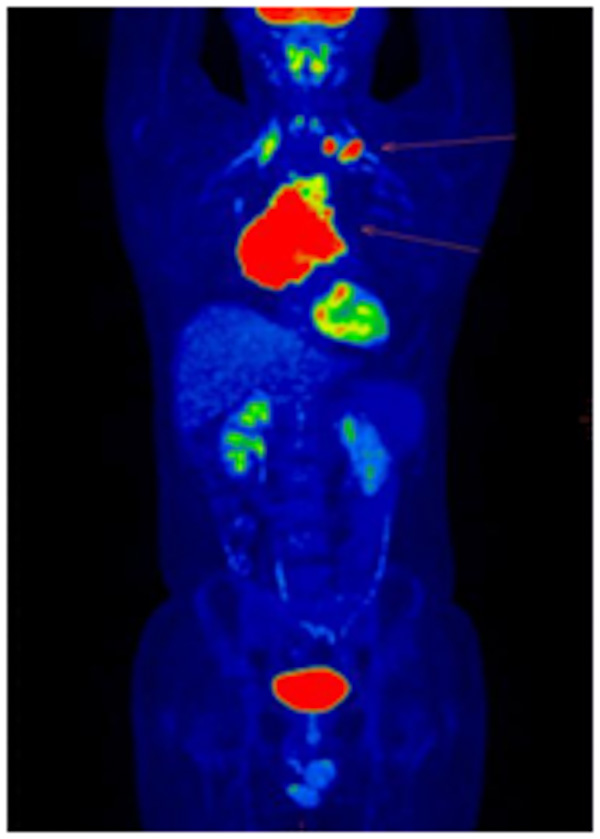

為確定治療方案,了解其他部位是否有淋巴瘤浸潤,進(jìn)行了PET-CT檢查,患者全身MIP圖一目了然!縱隔巨大腫塊淋巴瘤,左側(cè)鎖骨上窩淋巴結(jié)淋巴瘤浸潤。

治療4周期后,患者癥狀好轉(zhuǎn),再次到核醫(yī)學(xué)科行PET/CT顯像檢查,如圖所示。

治療后前上縱隔軟組織較前明顯縮小,仍有腫瘤活性組織存在;雙側(cè)鎖骨上窩、縱隔2組淋巴結(jié)均已吸收、滅活;右側(cè)胸膜及心包稍增厚。治療后病灶較前明顯縮小、減少,極大地緩解了患者相關(guān)臨床癥狀。